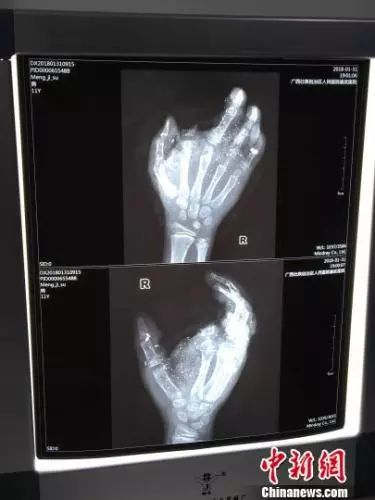

图为小明受伤的手掌骨骼图。 陈秋霞 摄

邕武医院医生兰天兵介绍,经检查发现,小明眼球有异物、肺部挫伤、右手臂和手指粉碎伤,食指断离。2月1日零点30分左右,兰天兵开始为孩子紧急做前臂皮瓣转移修复术、拇指、中指、环指再植手术,手术直至当天凌晨5点才完成。

兰天兵介绍,小明被送至南宁时,断离的食指并未一起带来。但由于断指也已经被炸得只剩一点,过于不完整,而手掌受损严重,几个手指已经无法供血,医生最终选择不接食指,抢救其他手指。兰天兵表示,目前小明的手掌已经恢复供血,有98%的痊愈率,恢复功能没有问题。